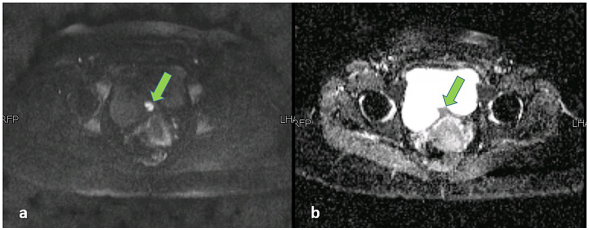

骨盆MRI显示增大的子宫,有多个子宫肌瘤和沿膀胱后壁的不规则混合信号强度肿块。该病变表现为膀胱内延伸,向后与子宫接触,脂肪平面不明显(图2)。经仔细检查,发现该病变引起了可能侵犯肌肉的外在印象。它的颅尾、AP和横向尺寸为36 x 29 x 21 mm,外观提示膀胱生长。然而,该病变的信号特征是出血性病变的典型特征,在T2加权序列上返回异质性低信号(图2),T1加权序列上的异质高信号,伴有斑片状对比增强(图2)(图3)和焦点扩散限制(图4)。鉴于患者的病史,MRI检查结果与膀胱子宫内膜异位症一致。

图4. 骨盆MRI图像。(a) 弥散加权成像和 (b) 表观弥散系数表明病灶内弥散受限的焦点区域(绿色箭头)